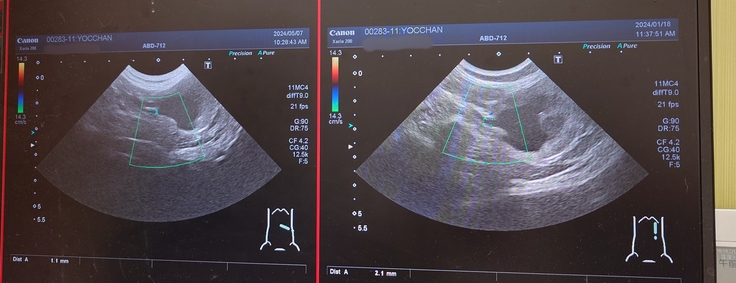

左側の拡大していた尿管。

画像の右側が前回のエコーで、左側が今回のエコー。

でも、尿管拡張していて腎盂腎臓が肥大している左側の尿管が2.1mmから1.1mmに細くなっていてこれは良い結果だったので安心しました😊